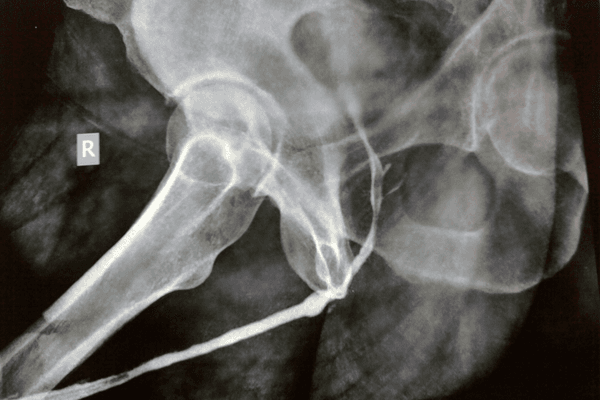

Initially, the patient is thoroughly evaluated using diagnostic imaging such as retrograde urethrography, cystoscopy, or other studies to determine the exact location, length, and severity of the stricture, which informs the surgeon’s decision to pursue either an excision and primary anastomosis or a substitution technique using a tissue graft. Under general or regional anesthesia in a sterile operating room, the surgeon makes a carefully measured incision in the perineum or penile skin, depending on the location of the affected urethral segment, to expose the compromised tissue while minimizing disruption to surrounding anatomical structures. In cases where the stricture is short and localized, the excision and primary anastomosis technique is preferred: the diseased segment is meticulously resected, and the healthy ends of the urethra are brought together in a tension-free manner using fine sutures, ensuring that the continuity of the urinary passage is promptly restored. Alternatively, when the stricture spans a longer segment or when direct re-approximation would result in undue tension, a substitution urethroplasty is performed by harvesting a graft—most commonly from the buccal mucosa—whose inherent resilience and compatibility render it an ideal substitute. The graft is carefully sutured into place after the urethral lumen is longitudinally incised to create an opening large enough to accommodate the replacement tissue, thereby reestablishing a patent channel for urine flow.